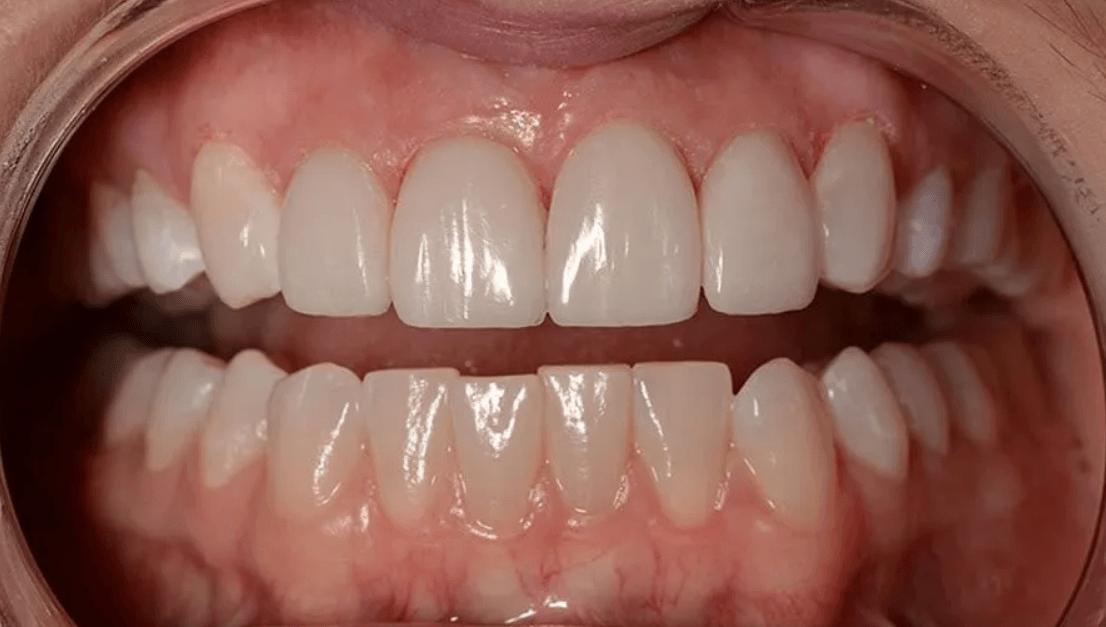

미아사거리 전체임플란트 전후

오랜 기간의 심한 치주염과 반복적 치아 파절로 통증·저작 장애가 심해진 환자분입니다. 보존 가능성을 충분히 평가한 뒤, 정밀 CT와 구강스캔을 바탕으로 상악 전체임플란트를 계획했습니다. 염증 치아를 단계적으로 정리하고 감염을 제어한 후 디지털 가이드로 안전하게 식립했습니다.

수술 과정에서 회복을 돕기 위해 자가혈/연어주사 등을 적용했고, 임시 보철로 적응 기간을 거친 뒤 최종 보철을 장착했습니다. 이후 정밀한 교합 조정으로 씹는 힘을 균형 있게 분산시켜 편안한 저작과 자연스러운 발음을 확보했습니다. 현재 환자분은 일상 식사가 한결 편해졌으며 심미적으로도 만족도가 높습니다. (개인 상태에 따라 계획·기간·결과는 달라질 수 있습니다.)